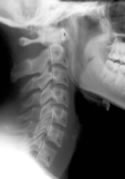

Chiropractic Improves Cervical Spine Lordosis

Cervical spine curve and chiropracticThe latest scientific research on whiplash injuries shows that automobile collisions can cause ligament damage to the cervical and lumbar spine. Numerous studies have shown that zygapophysial facet joints can be stretched during a rear end collision, and recent studies have shown injury to the anterior longitudinal ligament and the transverse ligament.

Identifying these ligamentous injuries, however, can be difficult. The ligaments themselves may be detected on MRI, but they cannot be seen on normal radiographs. It is more likely that the ligament injury will result in changes to the alignment of the cervical spine, and that can be detected with plain films.

A 2002 study1 compared the angle of cervical lordosis between whiplash patients and healthy controls. They found a statistically significant difference between the two groups, suggesting that whiplash injuries may indeed alter cervical spine alignment.

Now, a new study2 has shown that chiropractic treatment can improve cervical lordosis in patients after a motor vehicle collision.

The authors of this current study began with 13 patients who had been in a car crash. They obtained a neutral cervical radiograph taken in the natural standing position. Then, each patient was treated by a chiropractor. The patients had an average age of 24, and the average number of chiropractic adjustments was 17.7.

After a period of care, neutral radiographs were again taken, and both the pre- and post-treatment films were evaluated by a second chiropractor who was blinded to which films belonged to which patient.

The cervical curve was measured in each of the x-rays.

10 of the 13 patients showed an increase in the cervical lordosis found on x-ray. The average increase found in the patients was 6.4°.

One patient showed no change and two patients showed a decrease in cervical lordosis.

This study suggests that chiropractic adjustments do indeed increase cervical lordosis, which may be helpful for patients suffering from auto injuries. The sample size in this study was small, and the authors stress the need for further study into this matter.